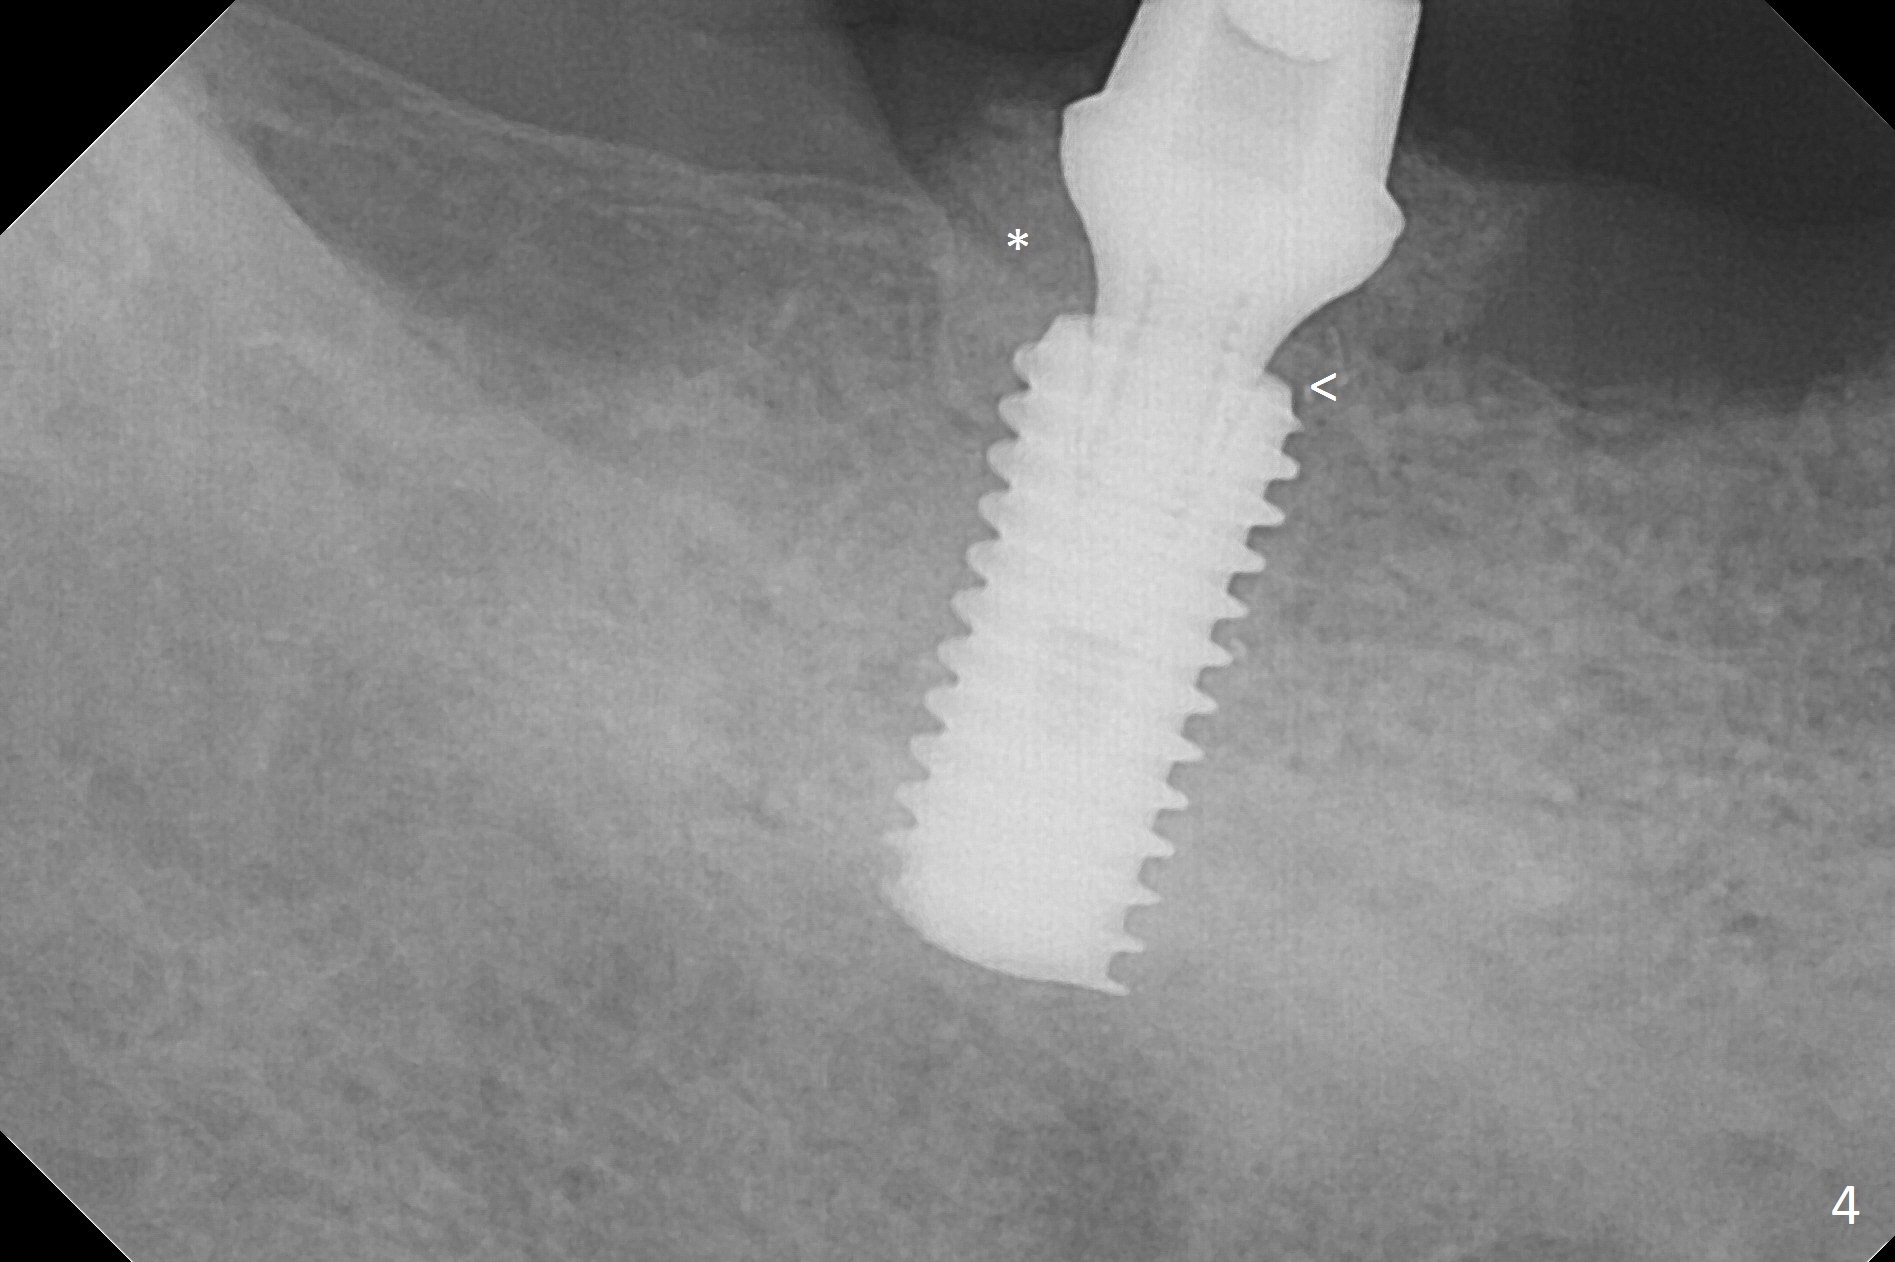

There are 2 challenges associated with #31 implant placement: indistinct Inferior Alveolar Canal (Fig.1-4) and difficulty in fabrication of a provisional (Fig.5). After placing a 5.5x13 mm implant (Fig.3 supracrestal (<)), it is removed for apical resection for ~ 2 mm; when it is reseated, it is subcrestal (Fig.5 <). A simplified temporary provisional (Fig.5 P) is fabricated around a 6.5x4(4) mm abutment (A) without adapting the lower RPD. The patient is advised not to wear the latter. When the socket heals, there will be 2 options: no provisional or a new one. The latter should have good retention to the abutment and no contact with the lower RPD in and out.